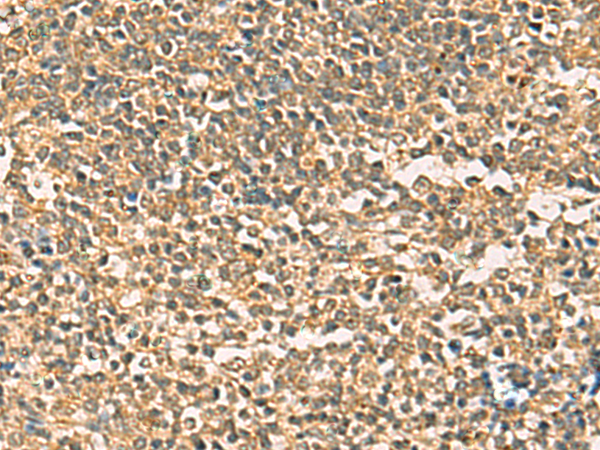

IHC positive control: |

Human liver cancer and Human colorectal cancer |